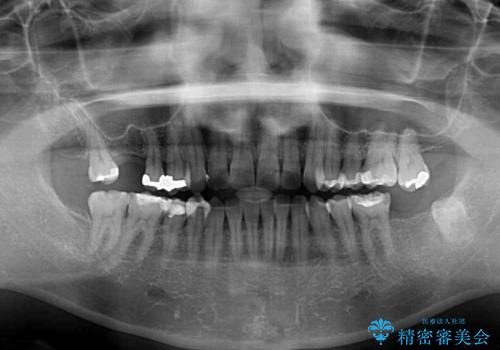

- 上下奥歯の欠損を気にして来院された患者様です。

以前矯正した後戻りにより前歯に叢生が認められたため、矯正治療の提案をしたところ、補綴治療と合わせて矯正治療を行うこととしました。

下顎欠損部はインプラントにて、上顎中間欠損部はブリッジによる補綴治療を行い、他にも気になっている銀歯をセラミックインレーやゴールドインレーにて修復治療を行うこととしました。

後戻りの程度は軽度であったため、インビザライン・ライトを用いて歯列を整えました。

再度後戻りするリスクを最小限に食い止めるため、下顎前歯の舌側を細いワイヤーで固定しました。